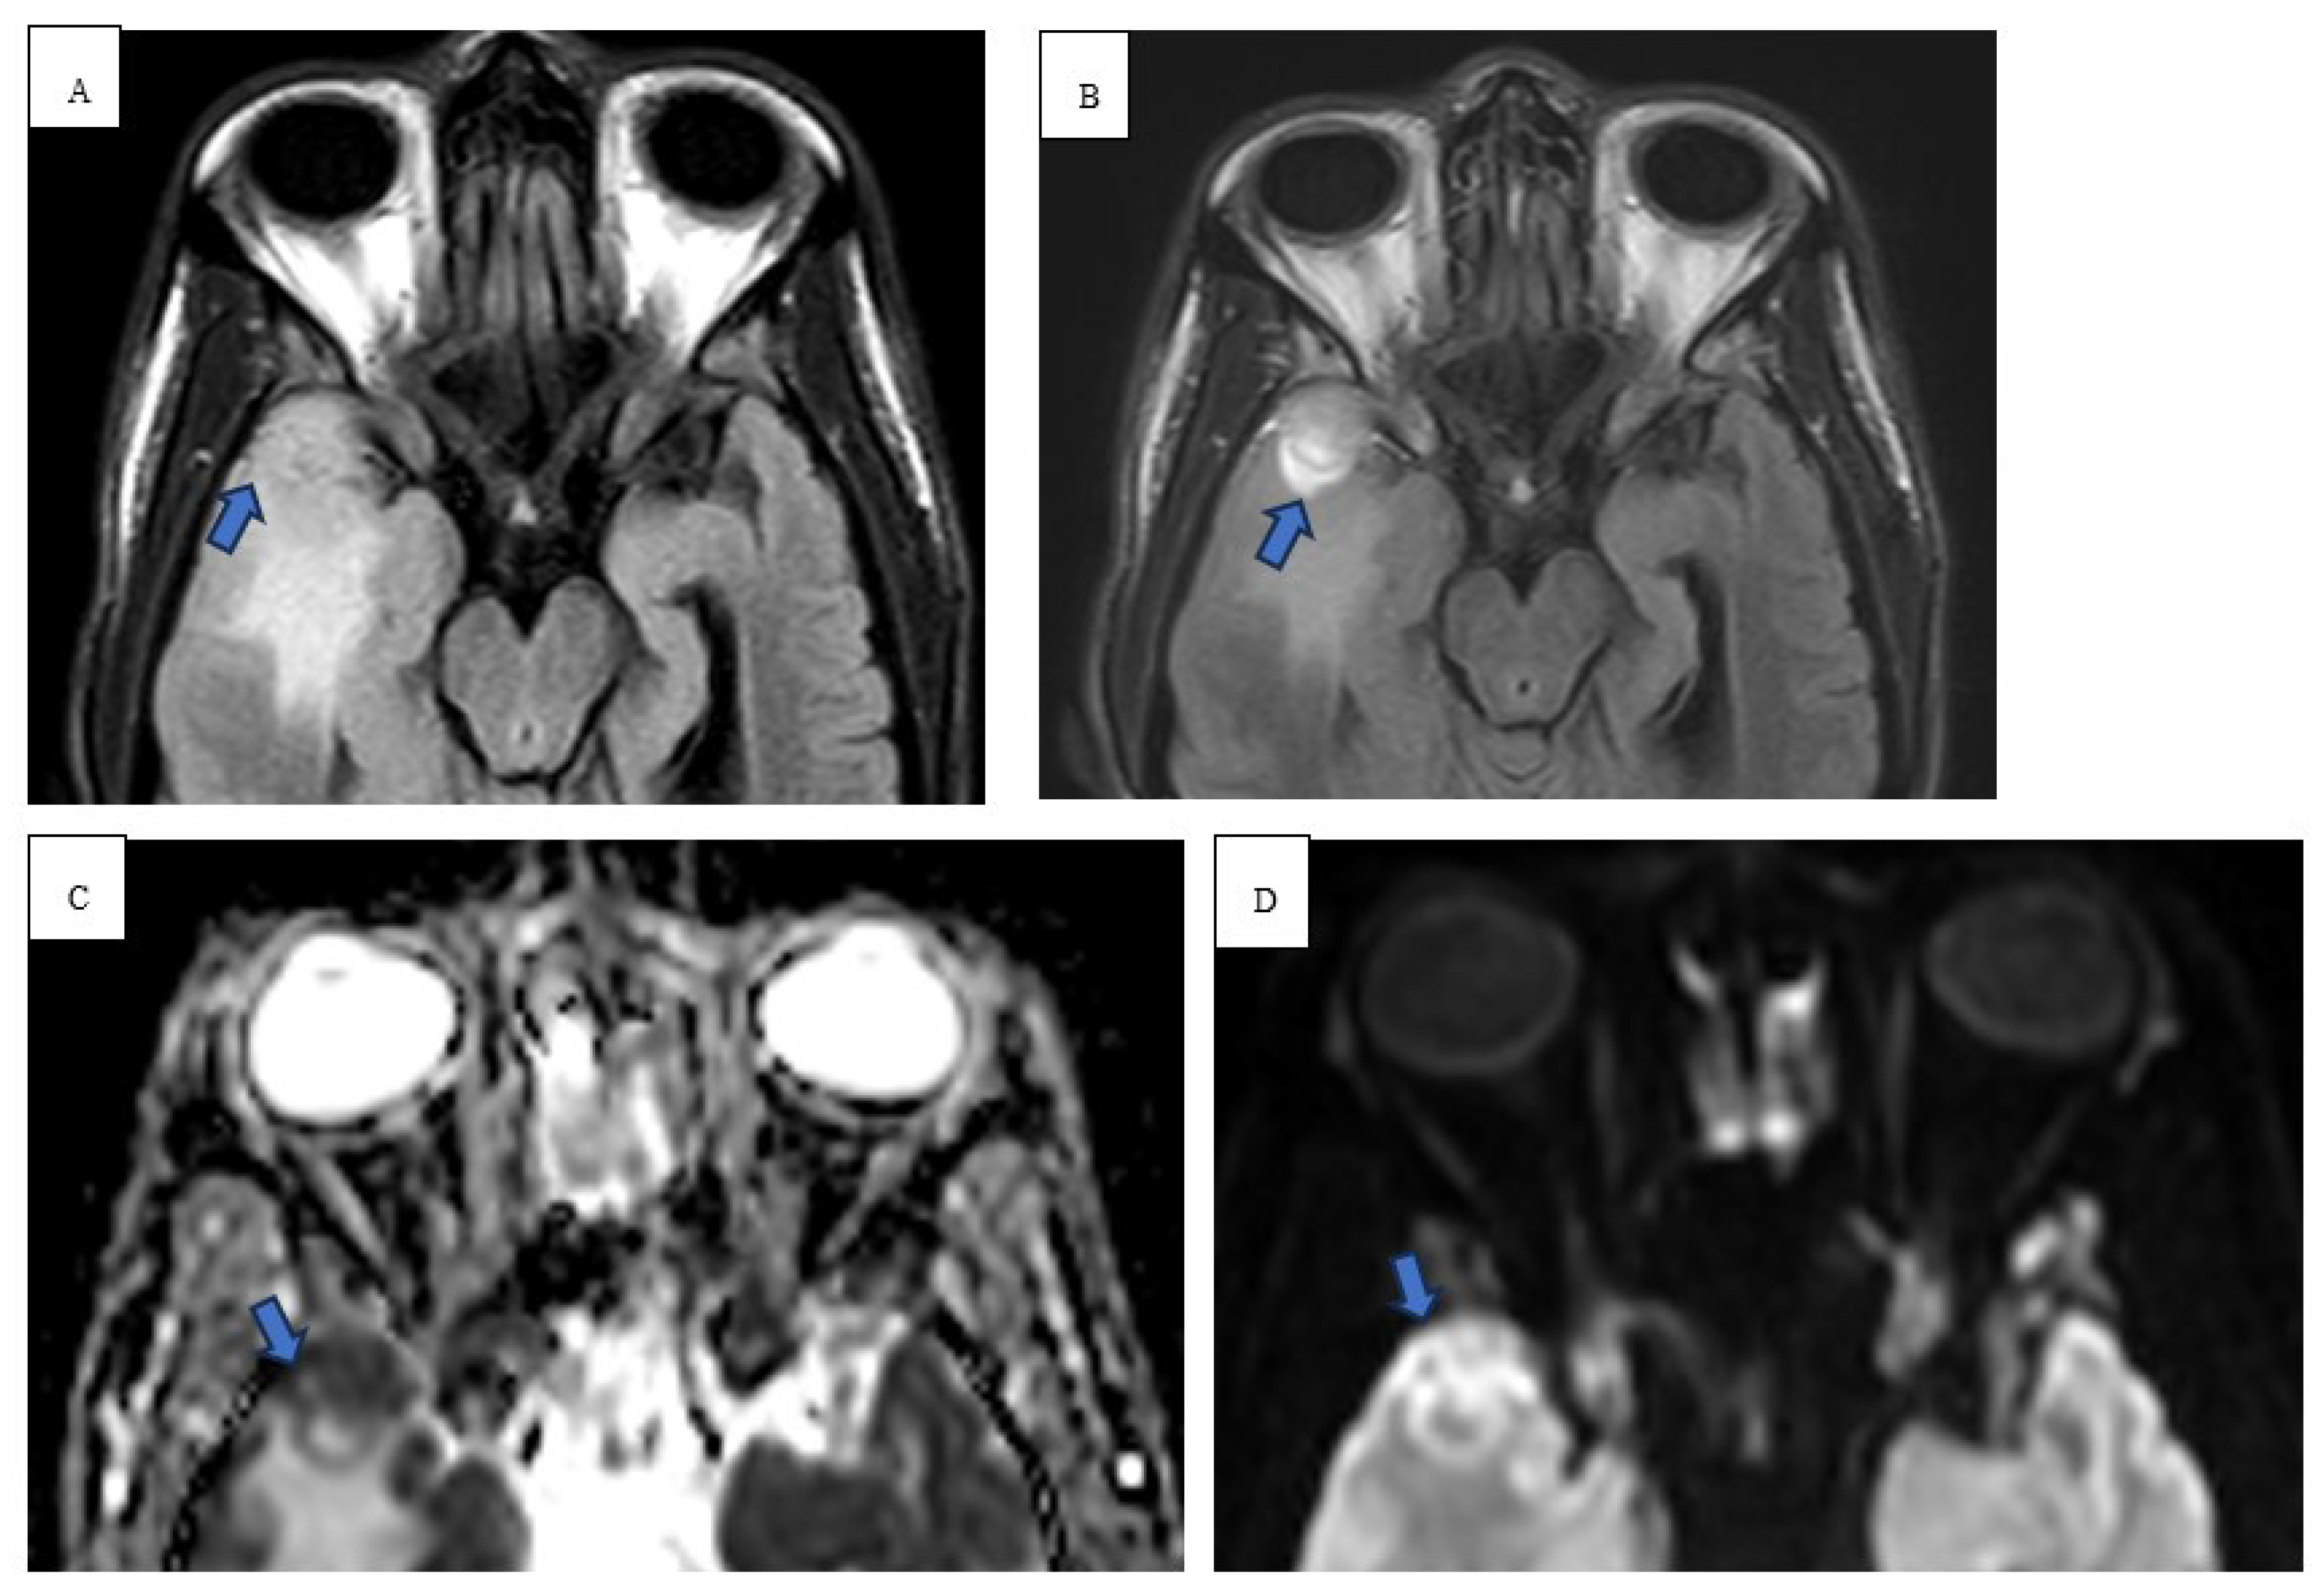

Thirty-one-year-old male with a history of untreated Mycobacterium nucogenicum isolated on bronchoscopy and bronchoalveolar lavage (BAL) culture 6 months prior, stage 4b mixed cellularity cHL. He was deemed asymptomatic from the mycobacterium infection, subsequent excisional lymph node biopsy confirmed the diagnosis, and the decision was made to start first line A-AVD regimen. The patient received 3 cycles with clinical improvement of his constitution symptoms. However, he subsequently presented to the hospital with 3-day onset of ataxia. He sustained a total of 3 falls with severe frontal headache that he rates as a 9/10 in severity. He denied loss of consciousness, problems with his vision, positional worsening, prior history of headaches, and neck pain. He reported worsening gait and generalized weakness over the last few days. Vital signs on admission were significant: 38.2C, 101 beats/min, and BP 113/52 mmHg. He developed intermittent fevers as high as 39.4C throughout his hospital course. Physical exam revealed abnormal finger to nose and heel to shin testing with broad based magnetic gait and impaired tandem gait. Labs revealed white blood cells (WBCs) 1.65x10(3)/mcL with absolute neutrophil count of 1.02x10(3)/mcL, ALP 100 u/L, ALT 75 u/L, AST 118 u/L. Lumbar puncture with cerebrospinal fluid (CSF) analysis did not indicate evidence of meningitis. Serology was positive for John Cunningham (JC) virus, cytomegalovirus (CMV), Ebstein Barr virus (EBV) but the CSF was negative for JC virus, CMV and herpes simplex virus (HSV). NCCT demonstrated vasogenic edema within the right temporal lobe. MRI brain with and without contrast revealed spherical 1.0 x 1.0 x 1.1 cm lesion that increased in size to 2.4 x 2.1 x 2.2 cm in 3 weeks (Figure 1 and Figure 2). Patient underwent a right pteronial craniotomy with stereotactic right temporal tip dural mass biopsy by neurosurgery. Histopathology confirmed cHL of the brain with reactive gliosis of the brain parenchyma. He was initiated on a dexamethasone taper over 5 days and salvage therapy with DHAP as inpatient and eventually immunotherapy with pembrolizumab with gemcitabine, vinorelbine, and liposomal doxorubicin (pembro-GVD) as outpatient. Repeat positron emission tomography (PET) CT scan demonstrated positive response and MRI of brain negative for recurrence of disease. Subsequently, the patient had progressive disease after 3 lines of therapy and deem stem cell transplant ineligible eventually transitioned to hospice and end of life care.

Radiologically, the first-line imaging modality should be a NCCT scan [14,15]. Characteristic findings include a hyperattenuating lesion associated with edema, while immunocompromised patients may have a more heterogenous or even hypoattenuating appearance [14]. MRI reveals iso- to hypointense lesion(s) on T1 weighted scans and iso- to hyperintensity on T2 weighted images [16]. DWI in immunocompetent patients show strong restricted diffusion with low ADC, however, lymphomatous spread in immunocompromised patients is more heterogenous with scattered lesions [17]. In high grade tumors and other metastatic tumors, there is high ADC due to significant vasogenic edema [15]. Our immunocompromised patient in case 1 revealed peripheral restricted diffusion on DWI with T1 isotensity, T2/FLAIR central hyperintensity, and peripheral T2/FLAIR hypotensity (Figure 1 and Figure 2). In a similar sense, case 2 demonstrated restricted diffusion on DWI and low ADC (Figure 3).

Figure 1. Pretreatment sagittal T1 (A), coronal T1 (B), axial T1 (C) post-contrast images demonstrating homogenously enhancing spherical lesion that measured 2.4 x 2.1 x 2.2 cm with anterior pachymeningeal enhancement (red circle). Perfusion scan of cerebral blood volume (D) demonstrates relative value of 2.09 which was consistent with lymphoma.